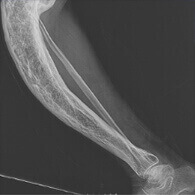

Деформация костей

Артрит и артроз Боль при движении и в состоянии покоя. Хруст. Затрудненное движение. Возникновение шпор и кистообразных структур. Деформация сустава. Полная неподвижность.

Остеохондроз и остеопороз Периодическое онемение конечностей. Боль в спине и позвоночнике. Боль в области сердца и ребер. Протрузия и грыжа диска в шейном отделе. Сосудистые нарушения.

Бурсит Сильный отек в области поврежденного сустава. Нарушение подвижности сустава или полная неподвижность конечности. Болезненные ощущения при пальпации. Покраснение кожи с нечеткими границами в области опухоли. Поражение гноем тканей. Заражение крови. Появление свищей. Полная потеря двигательной способности сустава.

Синовит Скованность движений. Боль при пальпации. Поражение больших суставов. Интенсивные неприятные ощущения и отечность в пораженной области. Заражение крови. Паралич.

При отсутствии правильного лечения больные суставы дают тяжелейшие осложнения на весь организм. Во избежание непоправимых последствий в виде частичного или полного паралича приступайте к лечению как можно скорее!